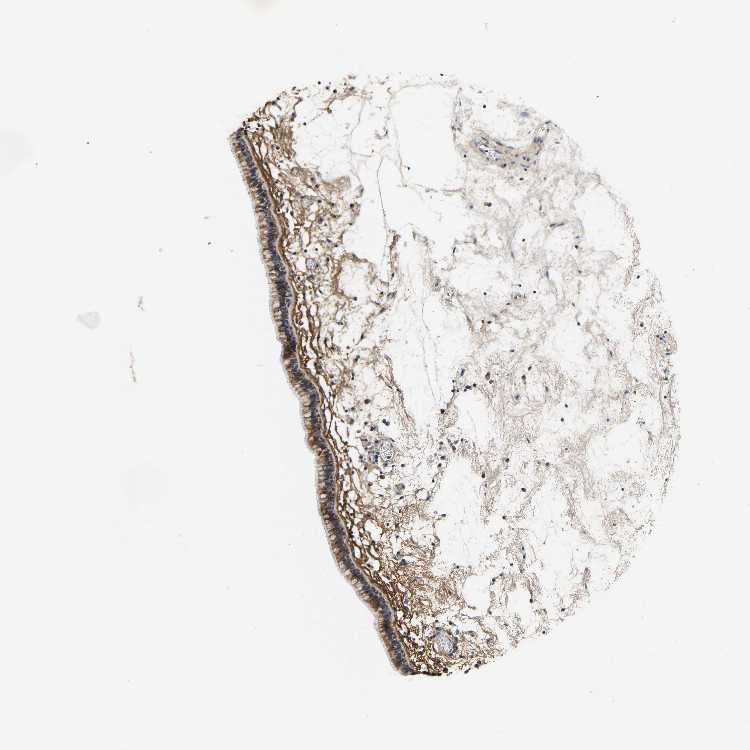

TISSUE PRIMARY DATA NASOPHARYNX Show tissue menu

NASOPHARYNX - Antibody stainingi

Antibody staining in the annotated cell types in the current human tissue is reported as not detected, low, medium, or high, based on conventional immunohistochemistry profiling in selected tissues. This score is based on the combination of the staining intensity and fraction of stained cells.

Each image is clickable and will lead to virtual microscopy that enables deeper exploration of all samples and also displays staining intensity scores, fraction scores and subcellular localization as well as patient and tissue information for each sample.

Antibody HPA019803Antibody HPA019806Antibody HPA024133

Respiratory epithelial cells MediumLowMedium